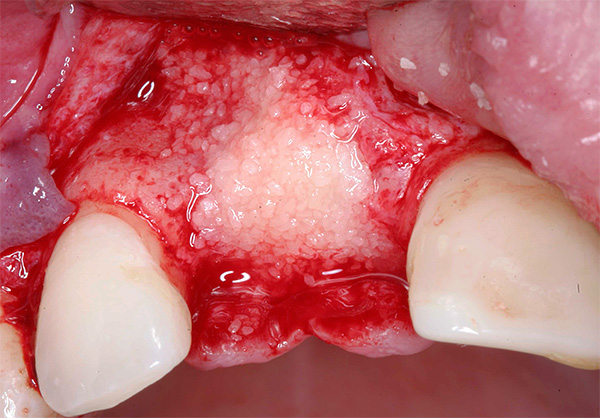

A foto abaixo mostra um exemplo de corrosão de um implante de baixa qualidade:

A qualidade do implante também desempenha um papel importante: quanto mais caro o sistema, mais materiais e tecnologias mais avançados são geralmente usados na fabricação da estrutura. As grandes empresas de implantes têm grandes orçamentos para gastar na melhoria de produtos e no desenvolvimento de tecnologias inovadoras.